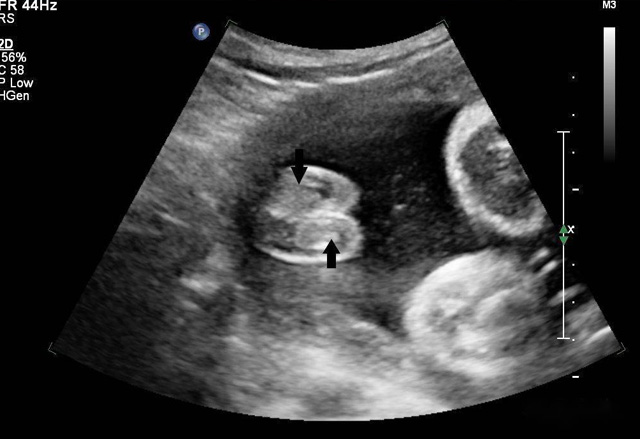

動態三維超聲成像有時間因素(心動周期)三維超聲成像分為靜態三維超聲成像和動態三維超聲成像,整體成像法重建感區域實時活動的三維圖像,稱為四維超聲心動。

三維超聲技術可用於心髒、腹腔、婦科、產科、小器官、血栓、血管成像等多方麵。